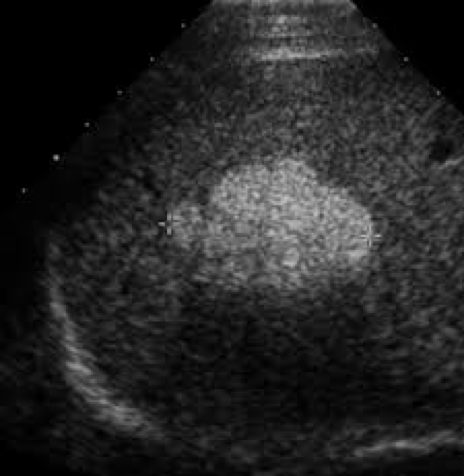

Acoustic enhancement:

- BecauseĀ ultrasound waves are hardly weakened in fluids, structures that are located behindĀ fluid-filledĀ spaces will appearĀ hyper-echoic shadow (brighter).

- Ultrasound is often used to Z **determine whether the structure is solid or cystic